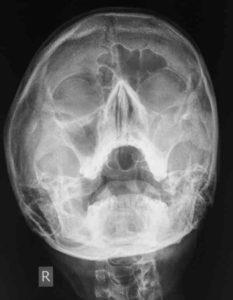

Как выглядит гайморит на снимке?

Здоровые околоносовые пазухи на снимке по оттенку схожи с глазницами. В случае развития воспаления они приобретают более темный оттенок с белесым, «молочным» содержимым. Обычно ровные края пазухи могут быть искривлены, кроме того, могут наблюдаться утолщения локально или по всему краю пазухи. Такая картина свидетельствует о том, что в пазухах развилась патология.

Расшифровкой рентгена занимаются отоларинголог и рентгенолог. На фото носовых пазух отмечаются потенциальные патологии и затемненные области. При анализе можно установить: наличие потенциально пораженных участков - затемненные или субзатемненные области, есть ли гайморит - осветленные области пазух носа.

После лечения насморка и заложенности врач может также установить характер болезни - вялотекущий, купированный, хронический, острый, наличие опухолей или кист.

Рентген снимок при гайморите выявляется горизонтальный уровень инфильтративного содержимого в определенной трети верхнечелюстной пазухи. Рентгенографическое исследование помогает ЛОР-врачу динамически отслеживать патологию при лечении. Существуют европейские исследования, указывающие не бессмысленность массового назначения рентгенограммы придаточных пазух нос при подозрении на воспаление синусов. Воспалительный процесс можно определить альтернативными методами (увеличение лейкоцитов крови, повышение температуры).

Рентгеновский снимок при гайморите показывает не только уровни жидкости при остром гайморите. Виды придаточных пазух носа у человека: 1. Лобные; 2. Верхнечелюстные; 3. Решетчатые; 4. Клиновидные. На одной рентгенограмме околоносовых пазух прослеживаются все описанные анатомические структуры. Рентгеновские синдром синусита зависят от морфологической формы патологии: • Экссудативная – характеризуется образованием инфильтрата, который по характеру может быть катаральным, серозным, гнойным; • Продуктивная – с гиперпластическими разрастаниями слизистой оболочки, полипами; • Альтернативная – атрофия, некроз, казеоз; • Аллергическая – подушкообразные разрастания оболочки пазух; • Смешанная. При остром гайморите нет необходимости в контрастировании полостей, панорамном снимке. Рентген признаки синусита: 1. Уменьшение пневмотизации полости; 2. Наличие уровня затемнения с верхней горизонтальной границей. В 2010 году исследователи штата Аризона заявили о важности рентген снимка не только при гайморите. Специфические симптомы на рентгенограмме выявляются при хроническом, аллергическом, идиопатическом синусите. Эксперименты проводились детям с хроническим кашлем. Доктор медицинских наук, профессор Вильсон выявить на основе рентгенографических снимков зависимости между хроническим гайморитом и длительным кашлем у детей. Для практической реализации исследования рентгенологи должны обучить принципам верификации хронических синуситов на рентген снимках. Для эксперимента отобрано 110 детей в возрасте 3-18 лет с длительностью кашля более 3 недель. Большинству представителей группы проведена антибиотикотерапия. Результат – у 63,7% детей было выявлено сочетание хронического гайморита с кашлем длительностью более месяца. На снимках 70% обследуемых определялся горизонтальный уровень затемнения. Только у 30% наблюдались другие морфологические проявления нозологии – пристеночное подушкообразное уплотнение, утолщение слизистой оболочки. Результаты были сообщены на съезде сообщества педиатров в 2012 году. Выводы удивили пульмонологов, которые не думали о серьезной зависимости между хроническим гайморитом и легочными заболеваниями с периодическим кашлем.